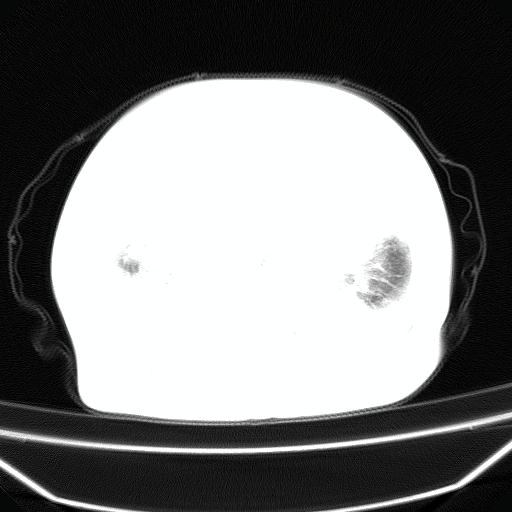

以下是引用jiangjing在2008-4-20 10:43:00的发言:[br]结合病史支持 冠心病[冠状动脉钙化],心功能不全,肺淤血、肺水肿,双侧胸腔与斜裂积液

以下是引用liuyue在2008-4-19 22:25:00的发言:[br]先考虑:1.心衰伴肺水肿、双侧胸腔积液、叶间积液、双下肺不完全性肺不张; [br] 2.冠状动脉粥样硬化。

以下是引用lijuanln在2008-4-19 23:05:00的发言:[br]两侧胸腔积液,肺水肿[br]心包积液[br]提示心衰